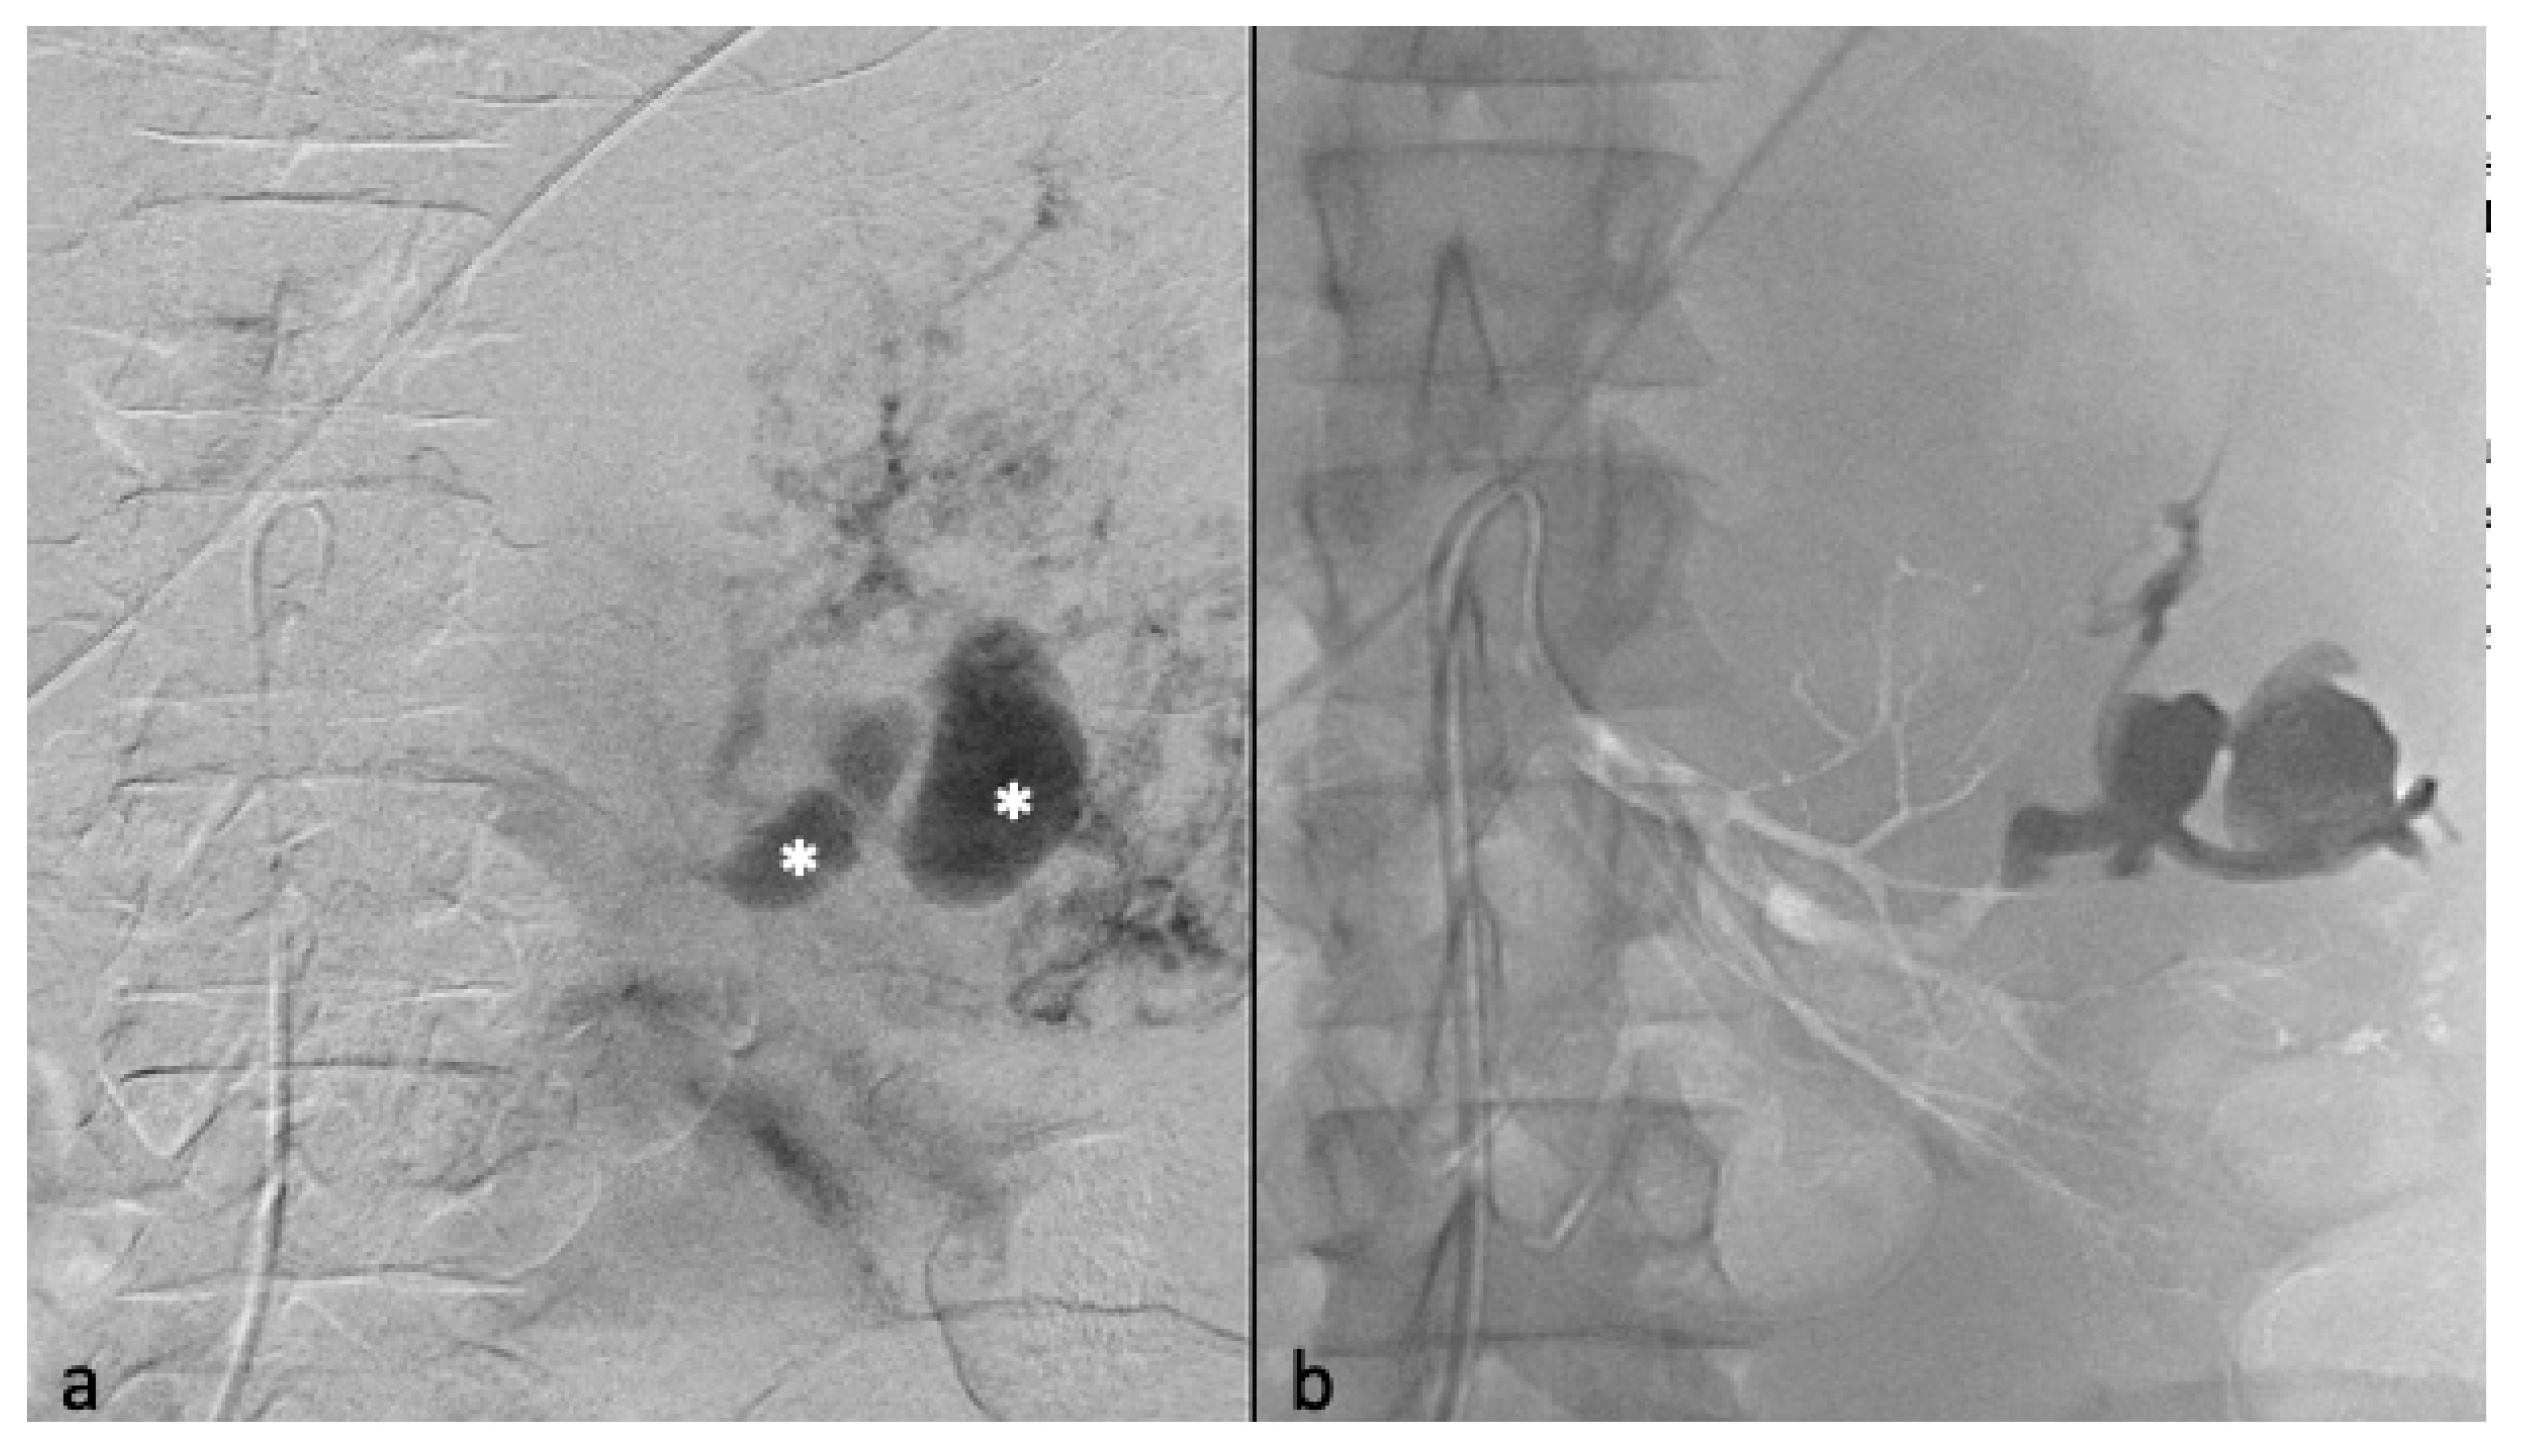

Figure 2.

Selective arterial embolization (TAE) of a large right AML. (a) Angiography shows two feeding arteries to the AML with multiples aneurysms. (b) The hypervascularity and dysplastic vessels of this AML are typical. (c) Final control after TAE of two arterial branches with ONYX 18 (6% EVOH) with technical success (lack of opacification of the AML).

Postembolization angiography performed through the 6-F catheter confirmed successful occlusion of the artery and the patency of other renal arteries branches. Technical success was defined as no opacification of the main feeding arteries and lack of AML staining on the post-TAE angiography after one embolization (primary technical success) or two (secondary technical success) (Figure 3).

The average arterial pedicle per AML was 1.4 (±0.8). Arterial pedicle count was the number of angiographically visible arterial pedicles that were a direct division of the renal artery and participated in the vascularization of the tumor. A high arterial pedicle count was significantly predictive of a second embolization (p < 0.01). The mean pre-embolization volume was 201.1 (±504.1) mm3. The majority of angiomyolipomas were exophytic (96%, n = 24). Ten patients had aneurysms on angiography (Figure 2a and Figure 3), including only five seen on pre-embolization imaging at diagnosis (Figure 1). Table 2 presents the different AML characteristics.